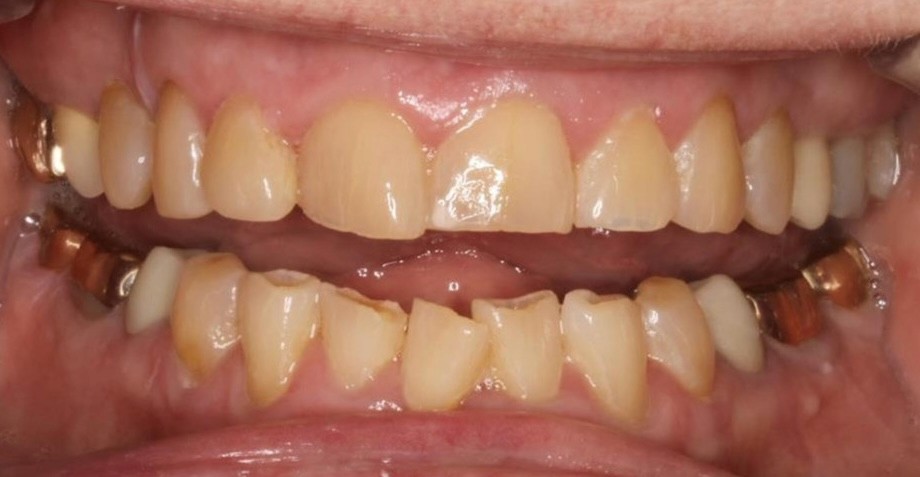

INTRAORAL